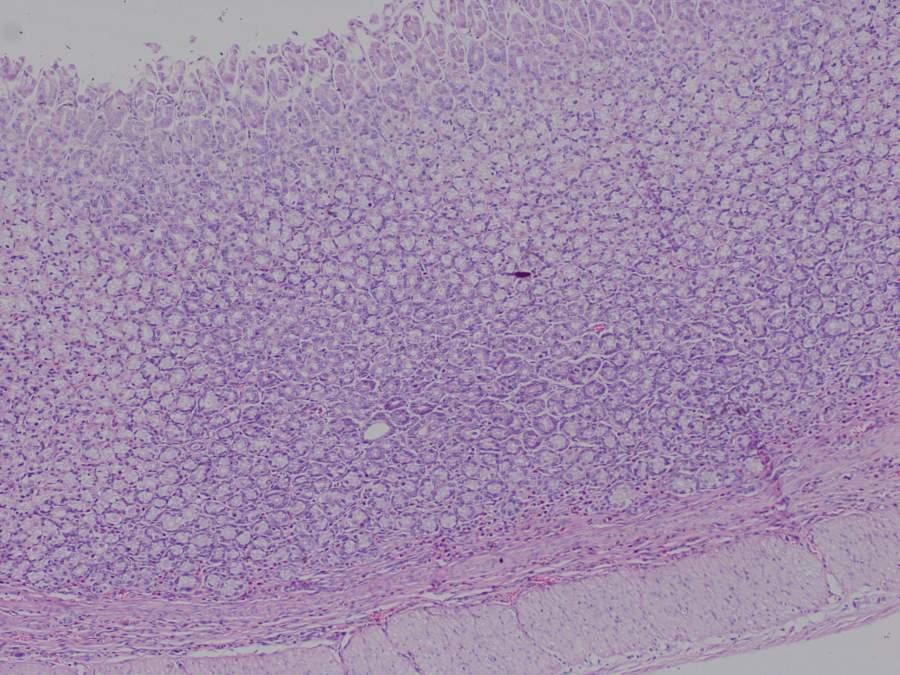

HE染色实验后的大鼠胃黏膜细胞观察(胃溃疡实验) 已有1人参与

求助大神帮描述一下各组的胃黏膜细胞情况,有无损伤:尽量描述的详细一点,万分感谢!!!! 低剂量1,100.jpg 高剂量2,200.jpg 和厚朴酚组1,200.jpg 空白组1,100.jpg 生药组1,100.jpg |